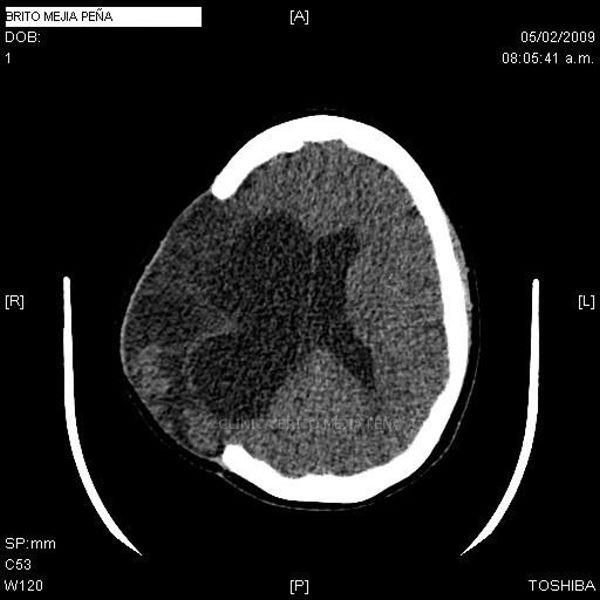

Envíado por BMP Imágenes Diagnósticas

BMP Imágenes Diagnósticas